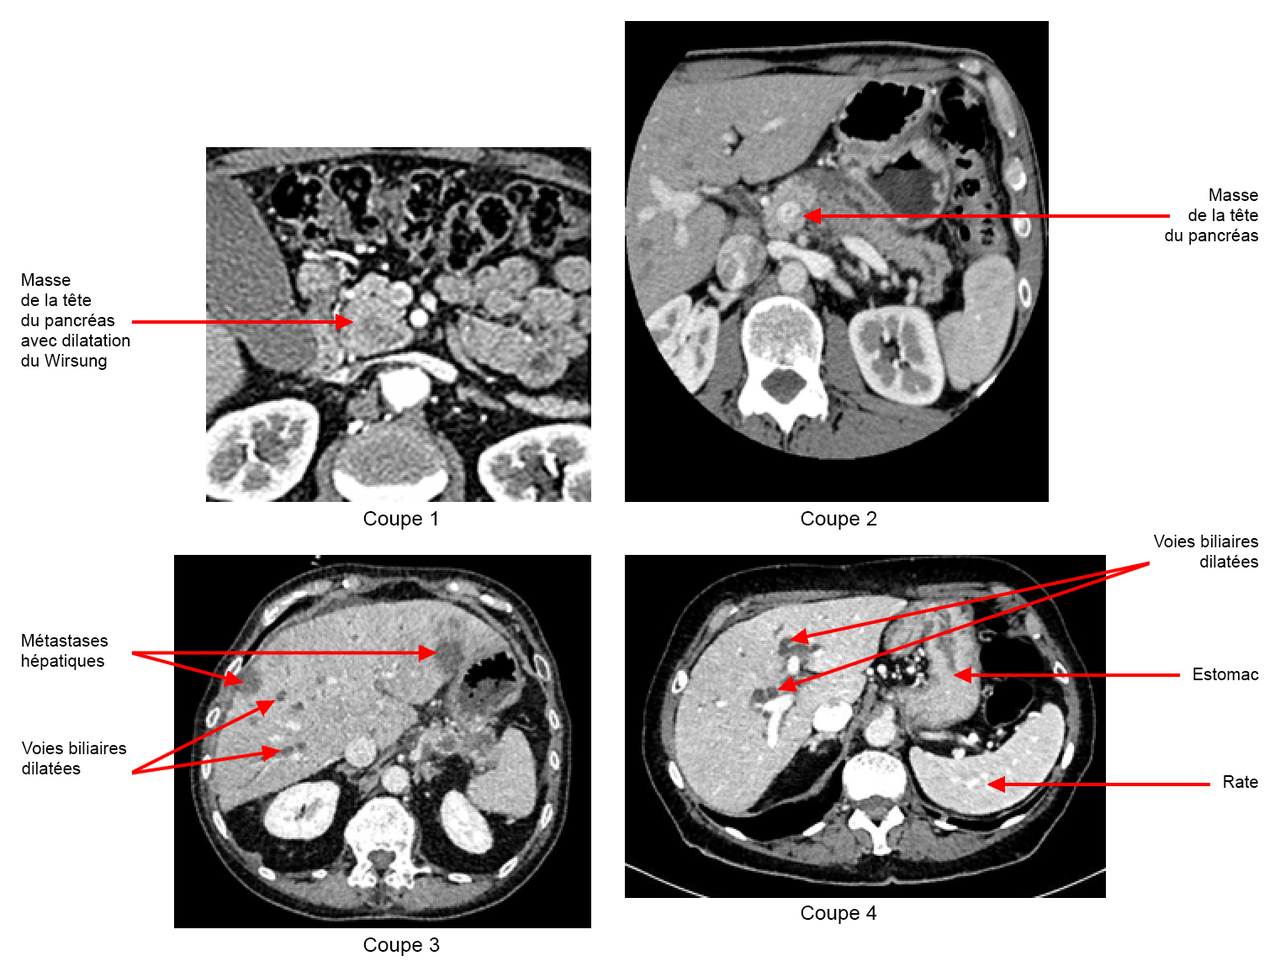

Les hypodensités hépatiques sont probablement des métastases hépatiques, étant donné leur nombre, leur forme et surtout le contexte.

Figure 2 (Source : Elisabeth Capelle, La Revue du Praticien)

Vous faites donc le diagnostic d’angiocholite sur obstruction des voies biliaires par une tumeur de la tête du pancréas, associée à des images évocatrices de métastases hépatiques.